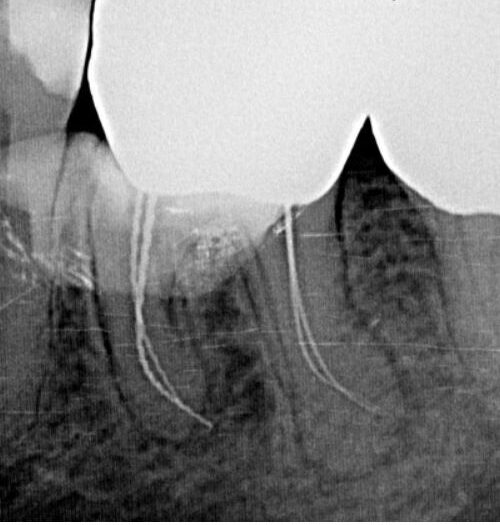

Radiografia de control arată dacă osul s-a refăcut și dacă nu există semne de reinfectare.

Radiografia de control este obligatorie după tratamentul endodontic.

Ea confirmă dacă obturația canalelor este completă și dacă vindecarea decurge normal.

Unii pacienți o refuză din teamă de radiații, dar aparatele moderne folosesc doze minime, complet sigure.

👉 Soluția: urmează planul de monitorizare recomandat de medic.

Radiografiile digitale oferă o imagine clară, fără riscuri pentru sănătate.